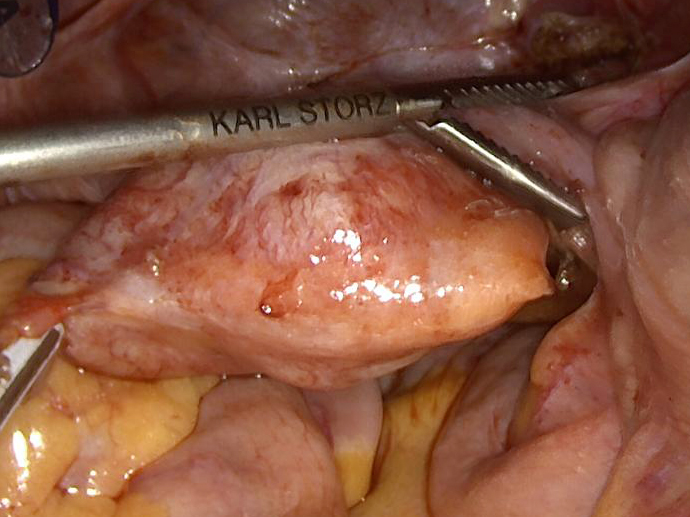

During laparoscopic surgery, the tumour proved to be confined to the appendix, with no other intra-abdominal findings (Panel A). The resection specimen disclosed a well circumscribed solid tumour, 4.2 cm in maximum diameter, with a homogeneously yellowish-white cut surface (Panels B and C).  Histologically, we observed a loose to densely cellular, spindled-cell neoplasia, arranged in fascicular and sweeping patterns (Panel D). Lymphoid aggregates, sometimes forming lymphoid follicles with germinal centres, were  found distributed at the periphery and also throughout the tumour (Panels E and F). The neoplastic cells had sparse cytoplasm and elongated, bland nuclei with inconspicuous nucleoli; focal and moderate atypia was noted (Panel G). Mitotic activity was <5mitoses/10HPF. Haemorrhage or necrosis were not observed. Upon immunohistochemistry, there was diffuse and strong positivity for S100 protein (Panel H) and moderate positivity for GFAP (Panel I). CD117 marked intralesional mast cells, whereas the tumour cells were negative (Panel J). Desmin and smooth muscle actin were negative (not shown).